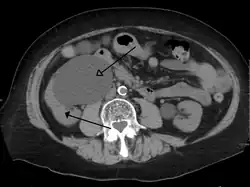

Massive hydronephrosis as marked by the arrow -